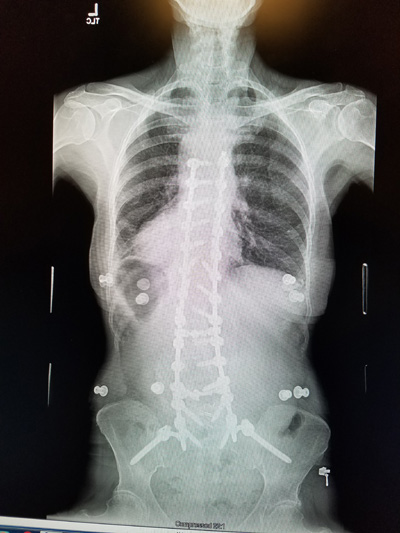

I still am doing the 4 mile hike. So with 3 times a week at PT and the hike my days are busy. Hope we can get started with our summer by Easter. Here are two views of my spine at my one year checkup.

Here are my January 2022 x-rays